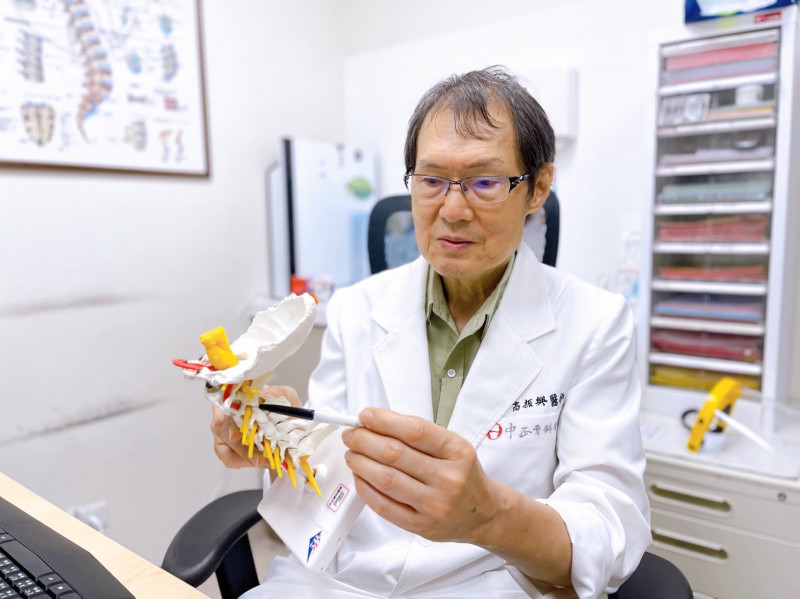

中正脊椎骨科院長高振興表示,頸椎後縱韌帶骨化症好發於頸椎,也可能發生於胸椎,後縱韌帶位於人體脊椎椎體的後緣,當這條韌帶因異常骨化性病變,導致椎管狹窄、壓迫脊髓與神經管,嚴重者甚至導致癱瘓、大小便失禁等。

高振興表示,後縱韌帶骨化症若壓迫到脊髓神經,就必須手術治療,所幸僅短節段,從頸部前位手術把壓在神經的骨化韌帶切除,骨化節數多的病患,大多採後位頸椎減壓手術;骨化短節數的病人,可考慮從頸前位把壓迫神經的骨化韌帶切除固定或做人工椎間盤,這樣的手術困難度較高,但也因節數短癒後情形較好。

頸椎後縱韌帶骨化症素有「東亞隱形殺手」之稱,由日本醫師發現的頸椎疾病,致病原因還未有定論,疑似與個人體質有關,東方人很常見,以日本人發生率1.9至4.3%最高,台灣人發病率也逐漸增加,病人常從無症狀到手腳發麻、行動不便,甚至四肢癱瘓,醫病不可輕忽。